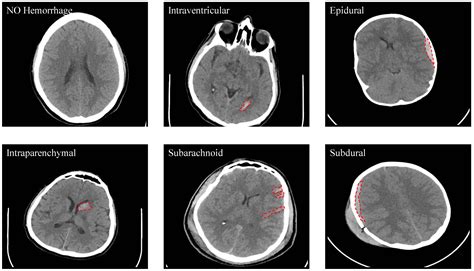

When blood leaks into the subarachnoid space, it appears as a bright, high-density (white) area on the scan, contrasting sharply with the darker, fluid-filled ventricles and brain tissue. The sensitivity of the scan is paramount; modern multidetector scanners are capable of detecting even very small amounts of subarachnoid blood. However, as time passes from the initial hemorrhage, the sensitivity of the scan decreases as the blood begins to dilute or break down.

• Interpretation by Radiologist: Careful examination for hyperdense areas in the sulci, cisterns, or fissures of the brain.

Despite the high sensitivity of the Subarachnoid Hemorrhage CT, there are instances where imaging can be deceptive. Small volumes of blood or specific anatomical locations can make interpretation difficult for the untrained eye. Moreover, in patients with severe anemia, the blood on a CT scan might appear less dense, making it harder to distinguish from the surrounding brain parenchyma. This phenomenon, known as the "isodense" sign, requires high-resolution imaging and expert clinical correlation.

• subarachnoid hemorrhage appearance on ct